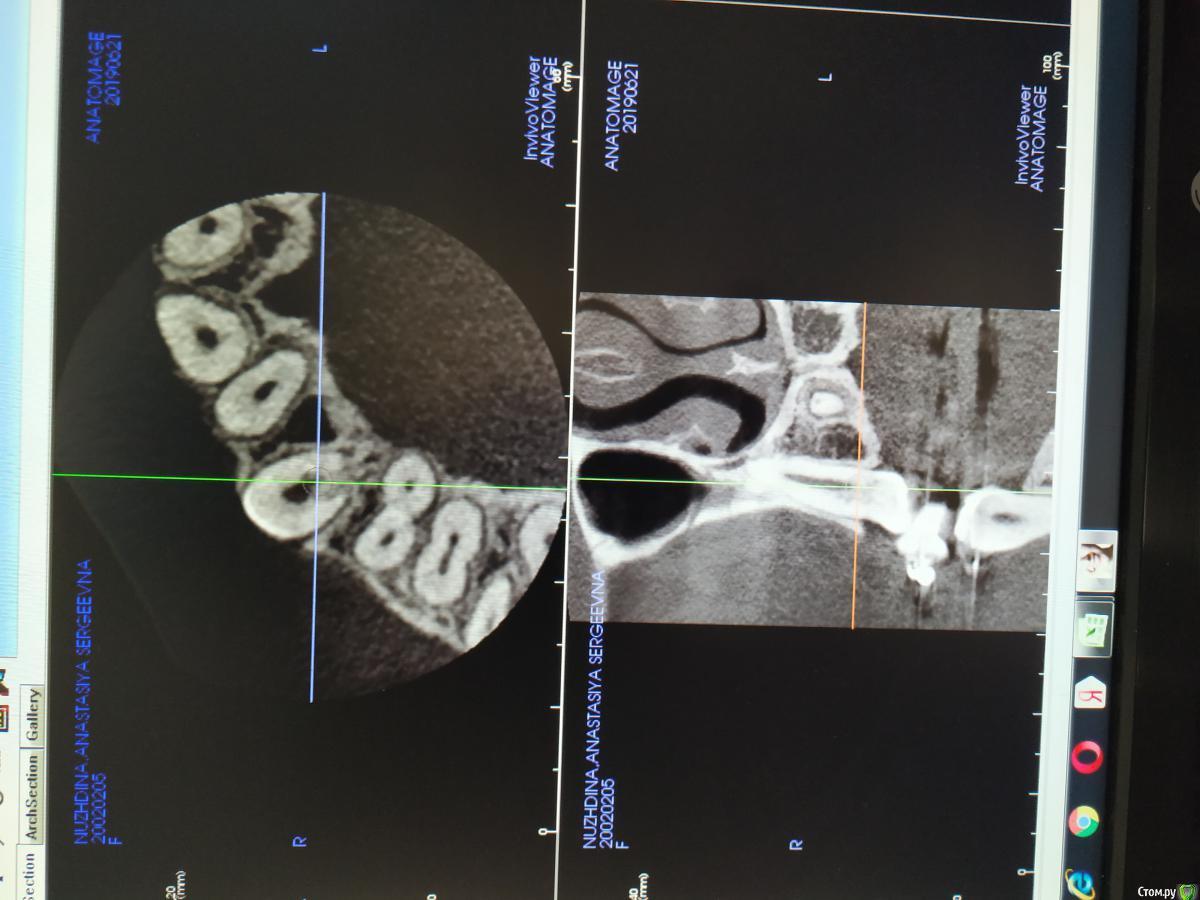

Здравствуйте. Ситуация такая: Ортодонт проводила лечение пациентки около года или немного больше, при попытке вытянуть клык соседние зубы наоборот стремились к клыку. В итоге был сделан 3Д снимок, фото прилагаю. Пациентка была только на консультации, лечится в др клинике.

Там ей предложили депульпировать и протезирование, но как я понимаю в зуб "врастает" костная ткань, соответственно после депульпирования есть риск получить просто резорбцию.

Возможно ли сделав остеоперфорацию в данной области ослабить сообщение с костной тканью, вытянуть зуб и уже потом депульпировать и запротезировать, когда зона риска будет над уровнем кости?